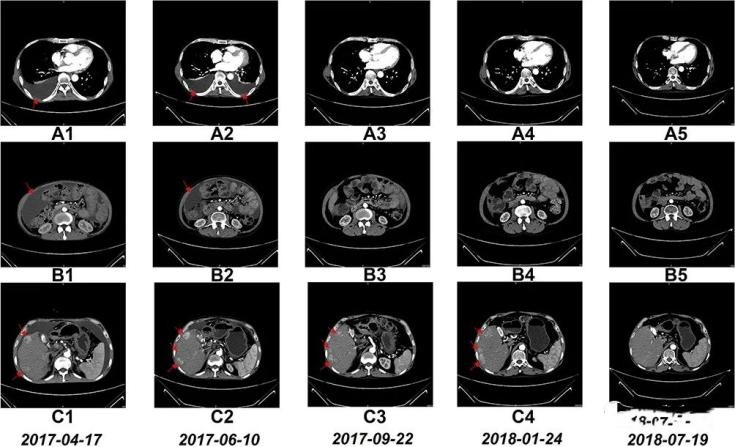

患者NK细胞治疗期间的CT扫描结果

CT扫描A1-5:6个疗程后胸腔积液清除。

CT扫描B1-5:6个疗程后腹水几近清除。

CT扫描C1-5:17疗程后肝右叶的瘤体明显缩小。